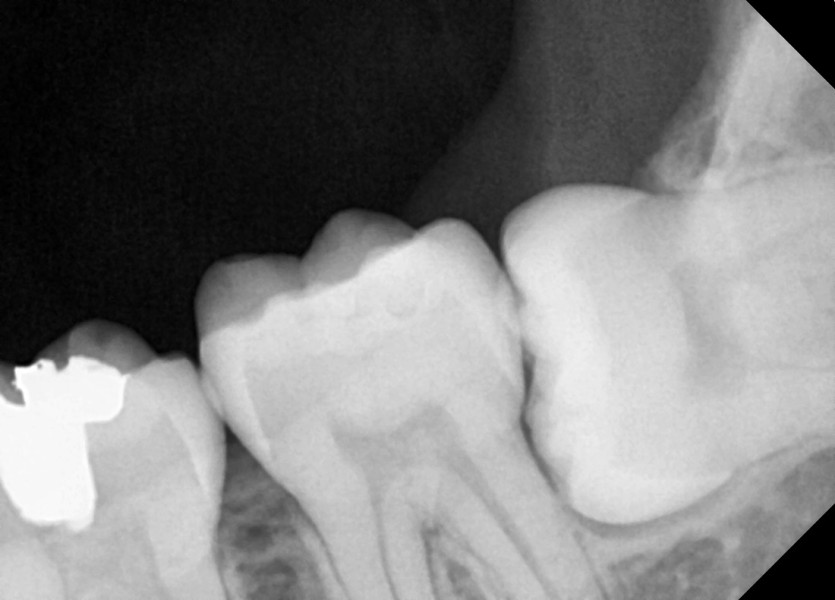

#38,48 사랑니 발치

구강 외과 전문의가 당일 발치했습니다.